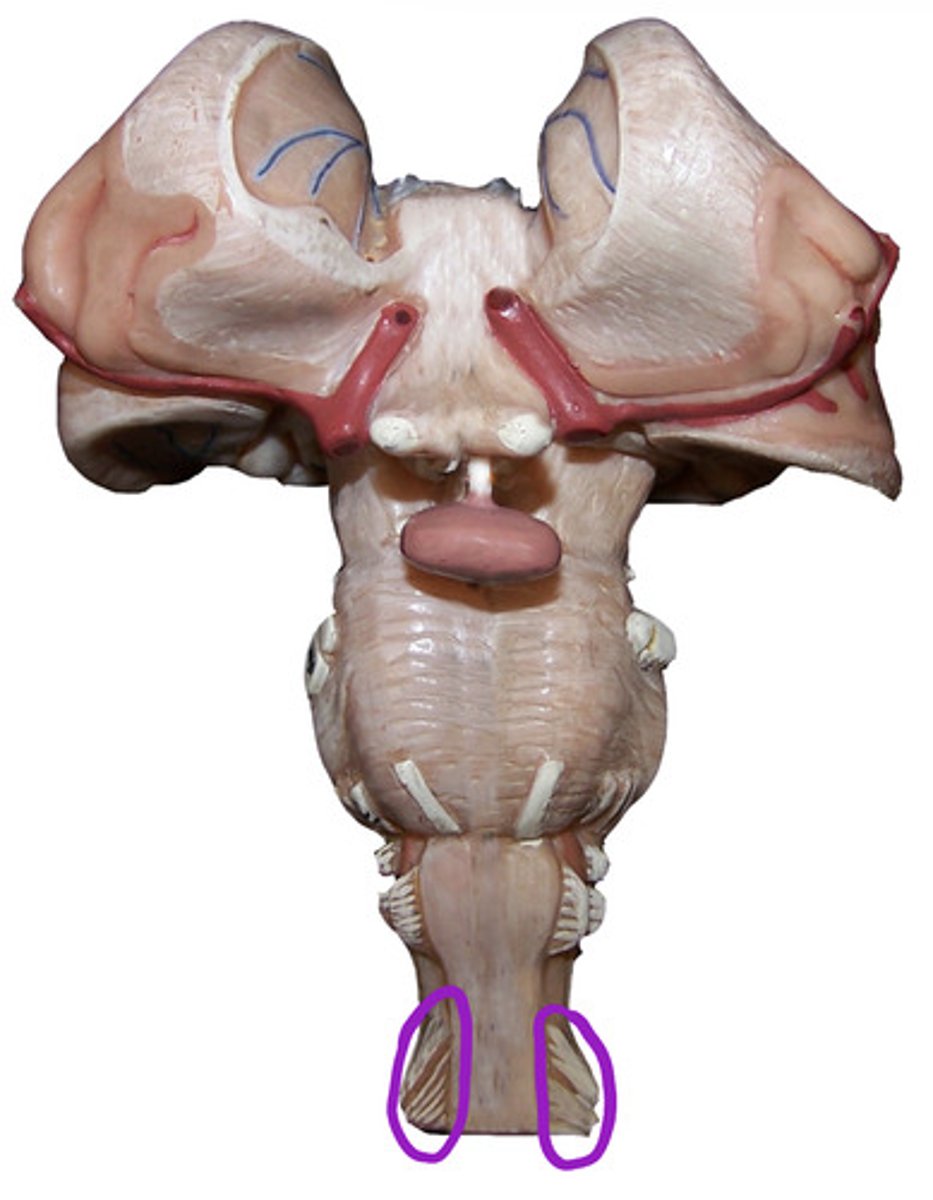

Lab 6: Brain and Cranial Nerves

Accessory Nerve

CN XI

Hypoglossal nerve

CN XII